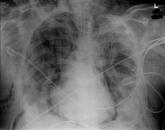

Pneumomediastinum and Pneumopericardium